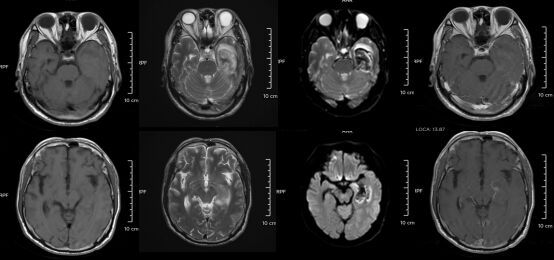

30岁小伙长期熬夜智力退回3岁,熬夜为何会诱发脑膜炎?-2.jpg △某单纯疱疹病毒性脑炎患者的医学影像。图源:浙江大学医学院附属第二医院

但如果拖延治疗,甚至会引发脑炎,可能出现癫痫、肢体偏瘫、尿潴留、认知功能障碍等严重后遗症,恢复时间长达3-6个月,甚至影响终身。